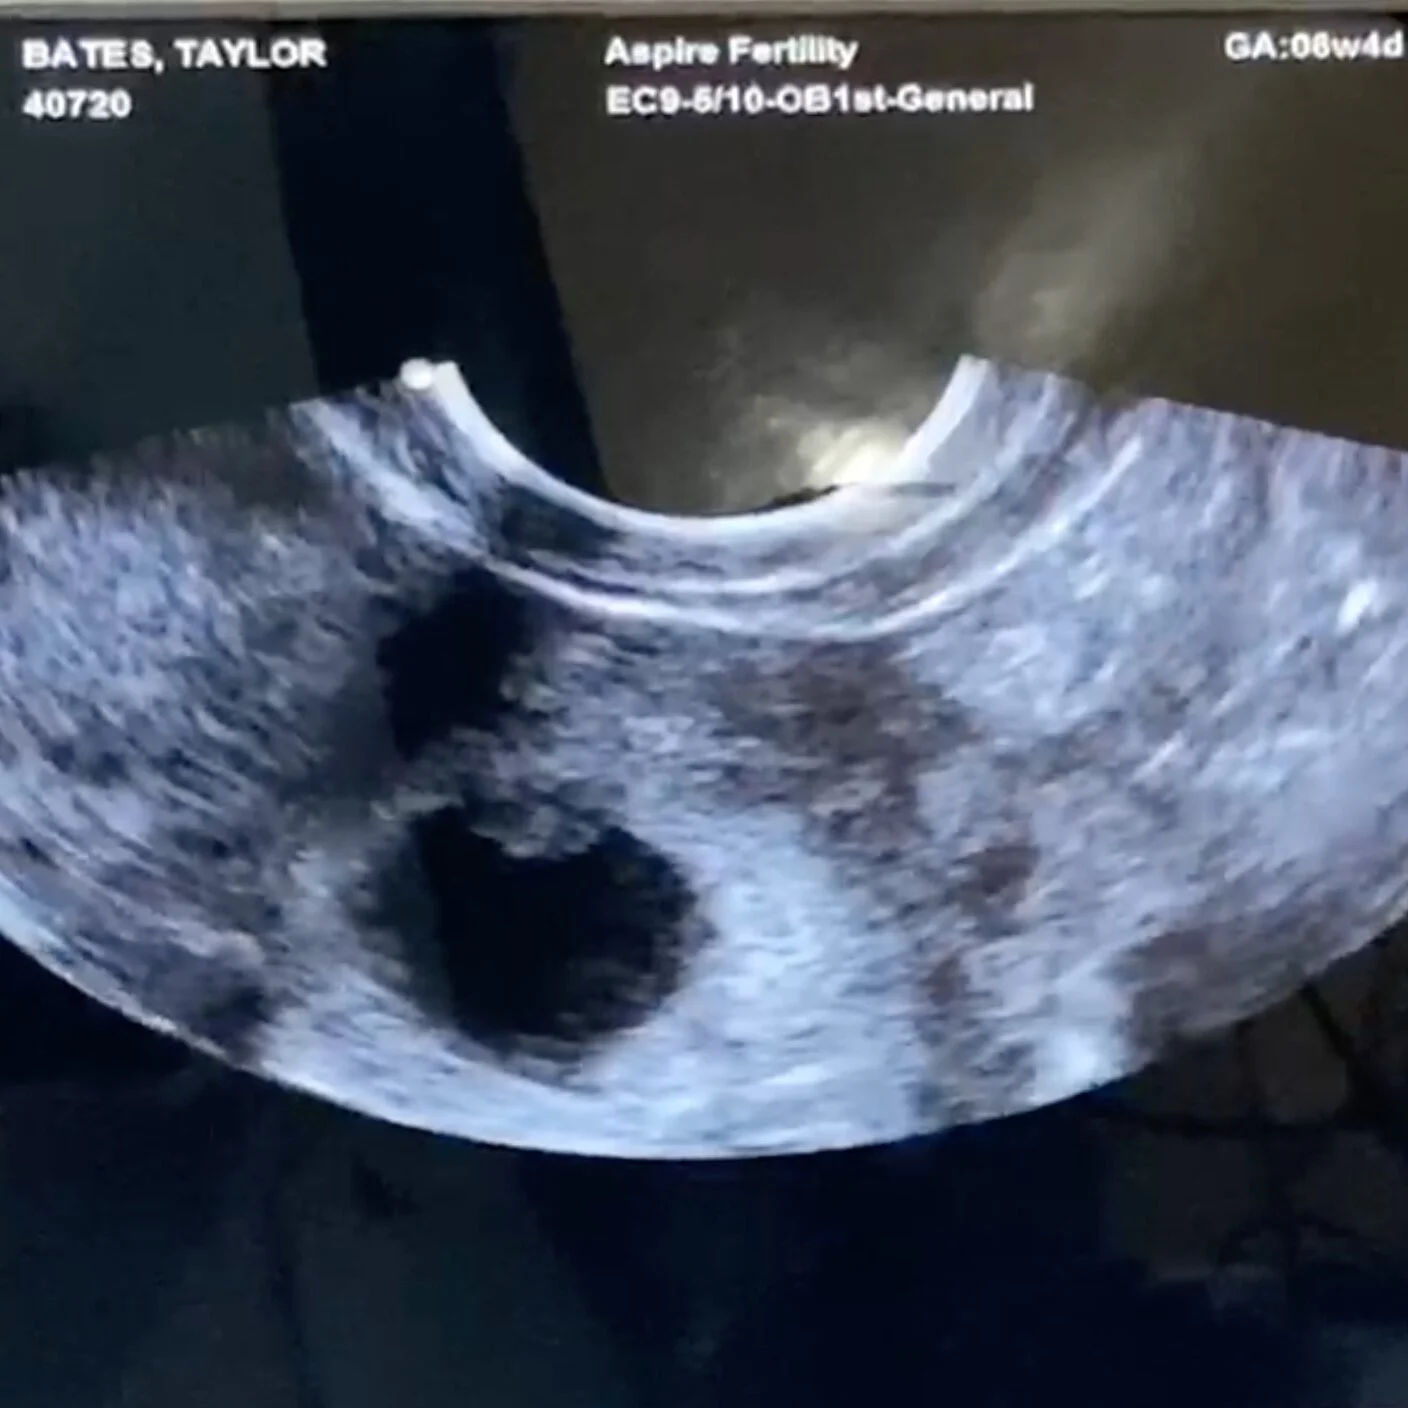

The biggest tiniest miracle happened today—we heard our baby’s heartbeat for the first time. It’s a sound we’ve been waiting to hear again for nearly two years since Ellis was stillborn.